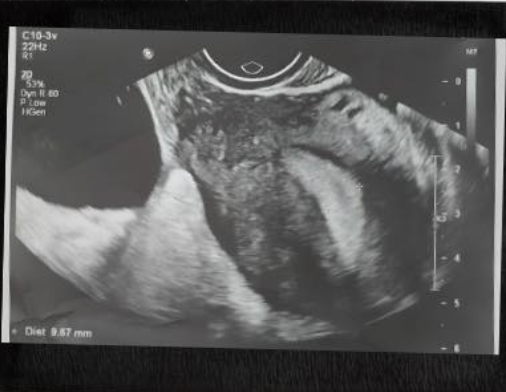

Chủ quan với cơn đau bụng bất thường, người phụ nữ suýt mất khả năng làm mẹ

Một trường hợp xoắn vòi tử cung hiếm gặp vừa được các bác sĩ Bệnh viện Phụ Sản Hà Nội phát hiện và xử trí kịp thời, cứu sản phụ thoát khỏi biến chứng nguy hiểm có thể đe dọa khả năng sinh sản.